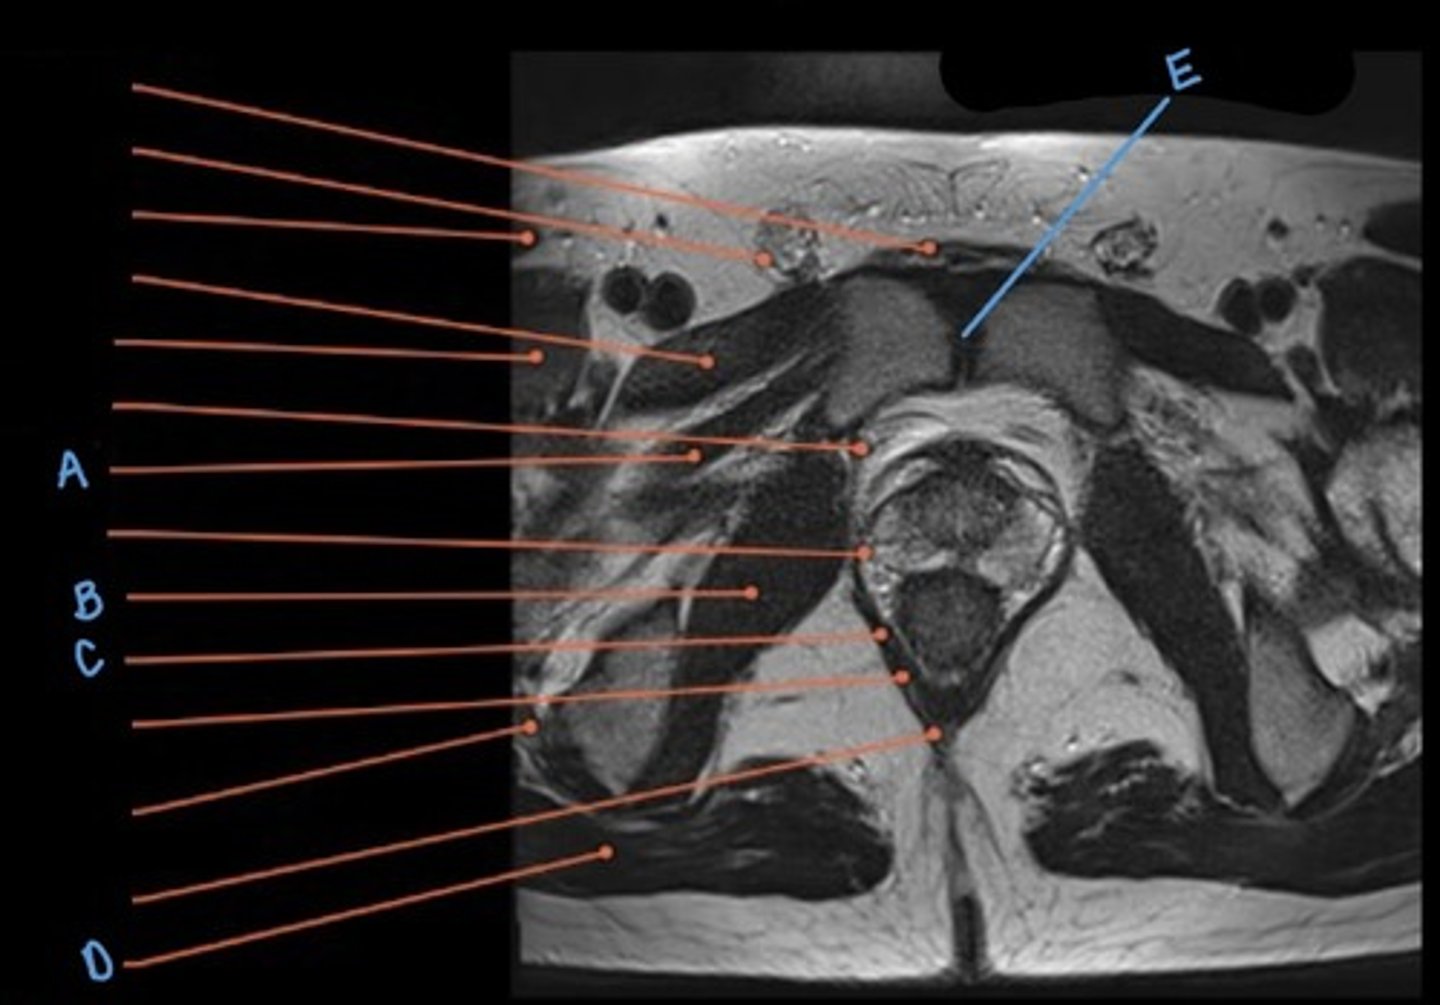

rectus abdominus muscle

A

bladder

B

prostate

C

obturator internus muscle

D

levator ani muscle (pubic diaphragm)

E

gluteus maximus muscle

F